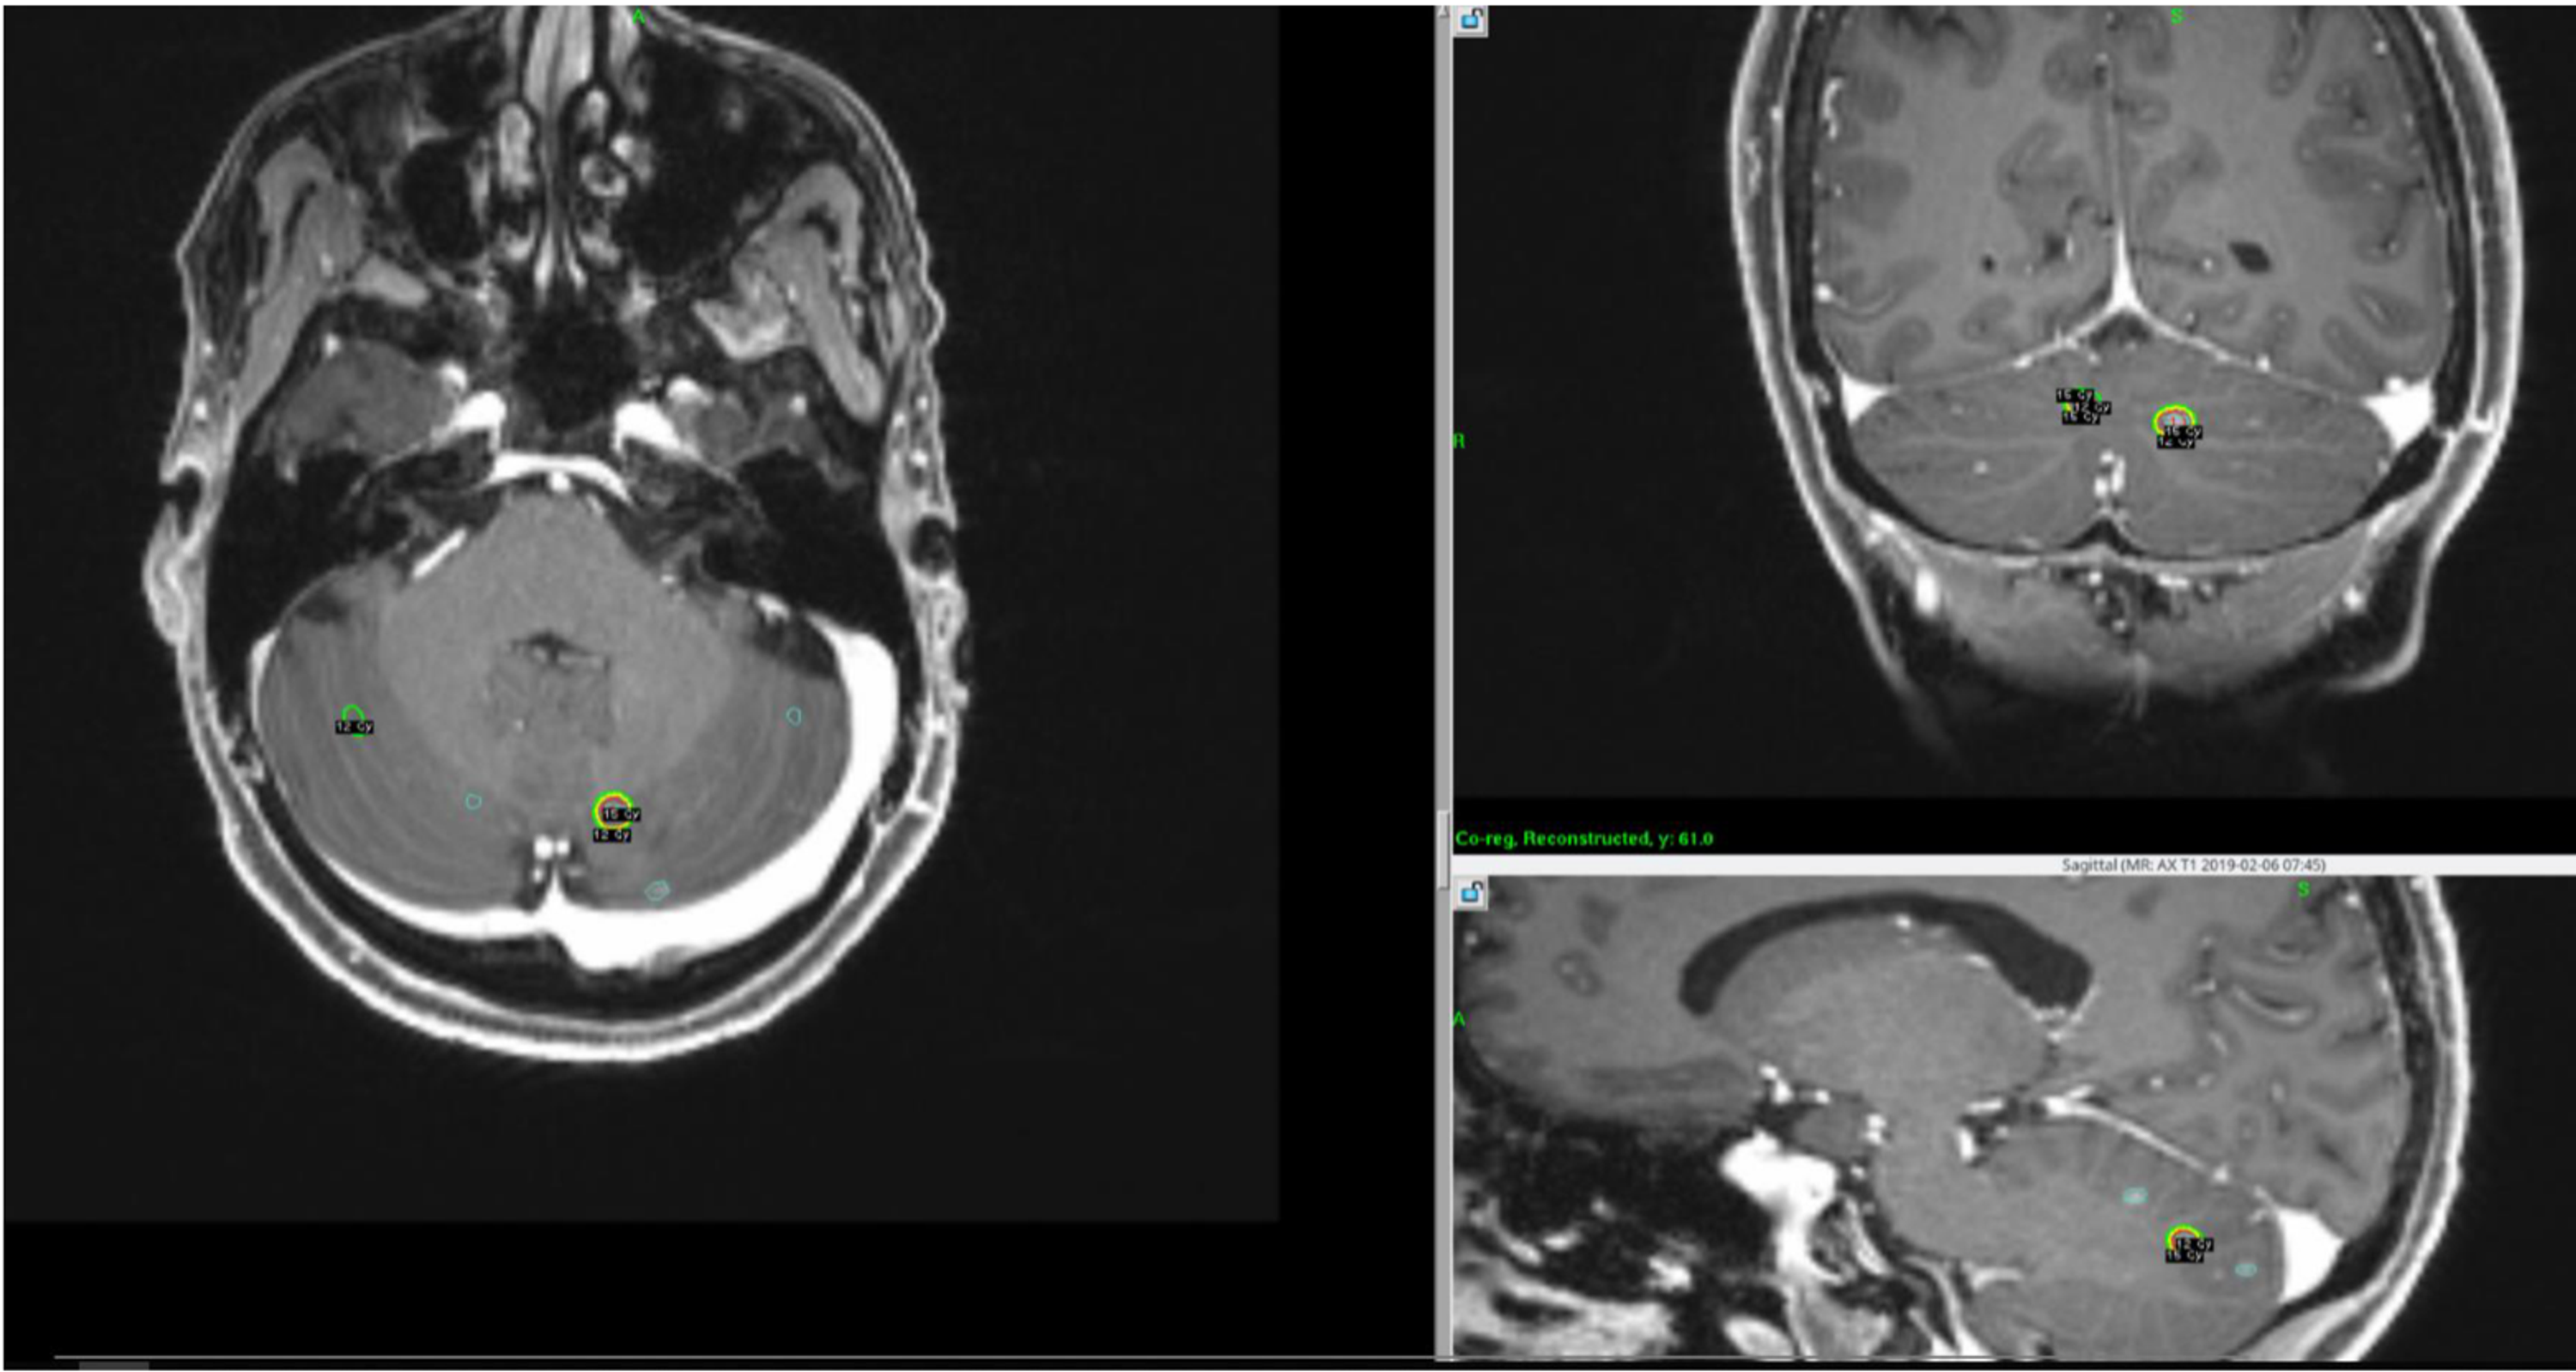

Source: redjournal.org